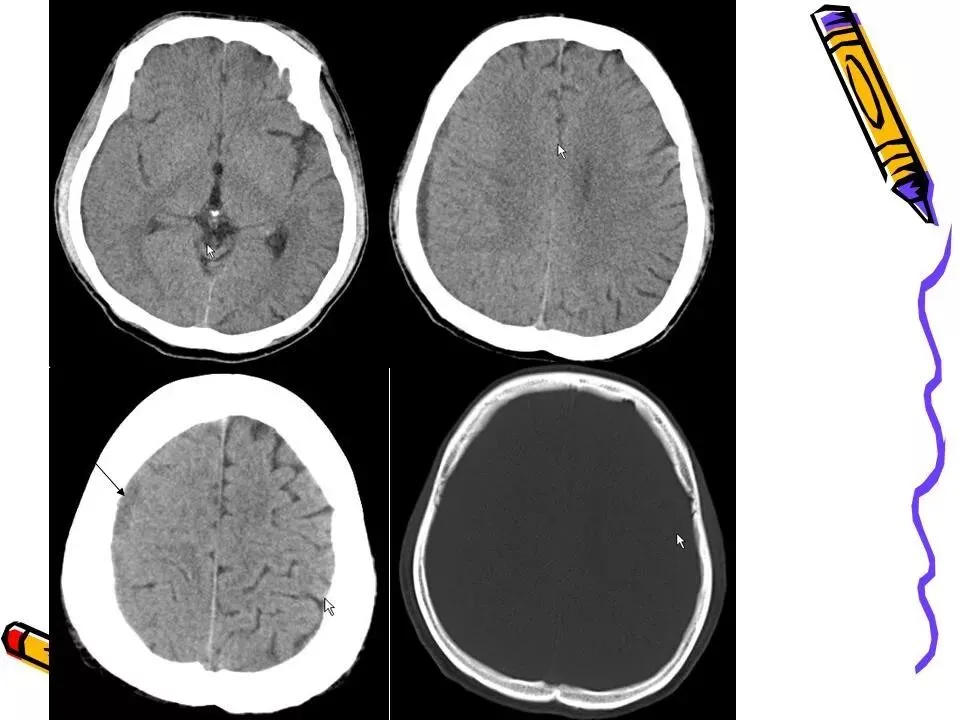

>常见颅脑外伤CT诊断(PPT)

常见颅脑外伤CT诊断(PPT)